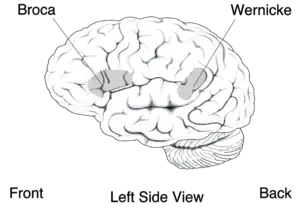

Broca's area (speech production) and Wernicke's area (language comprehension) | |